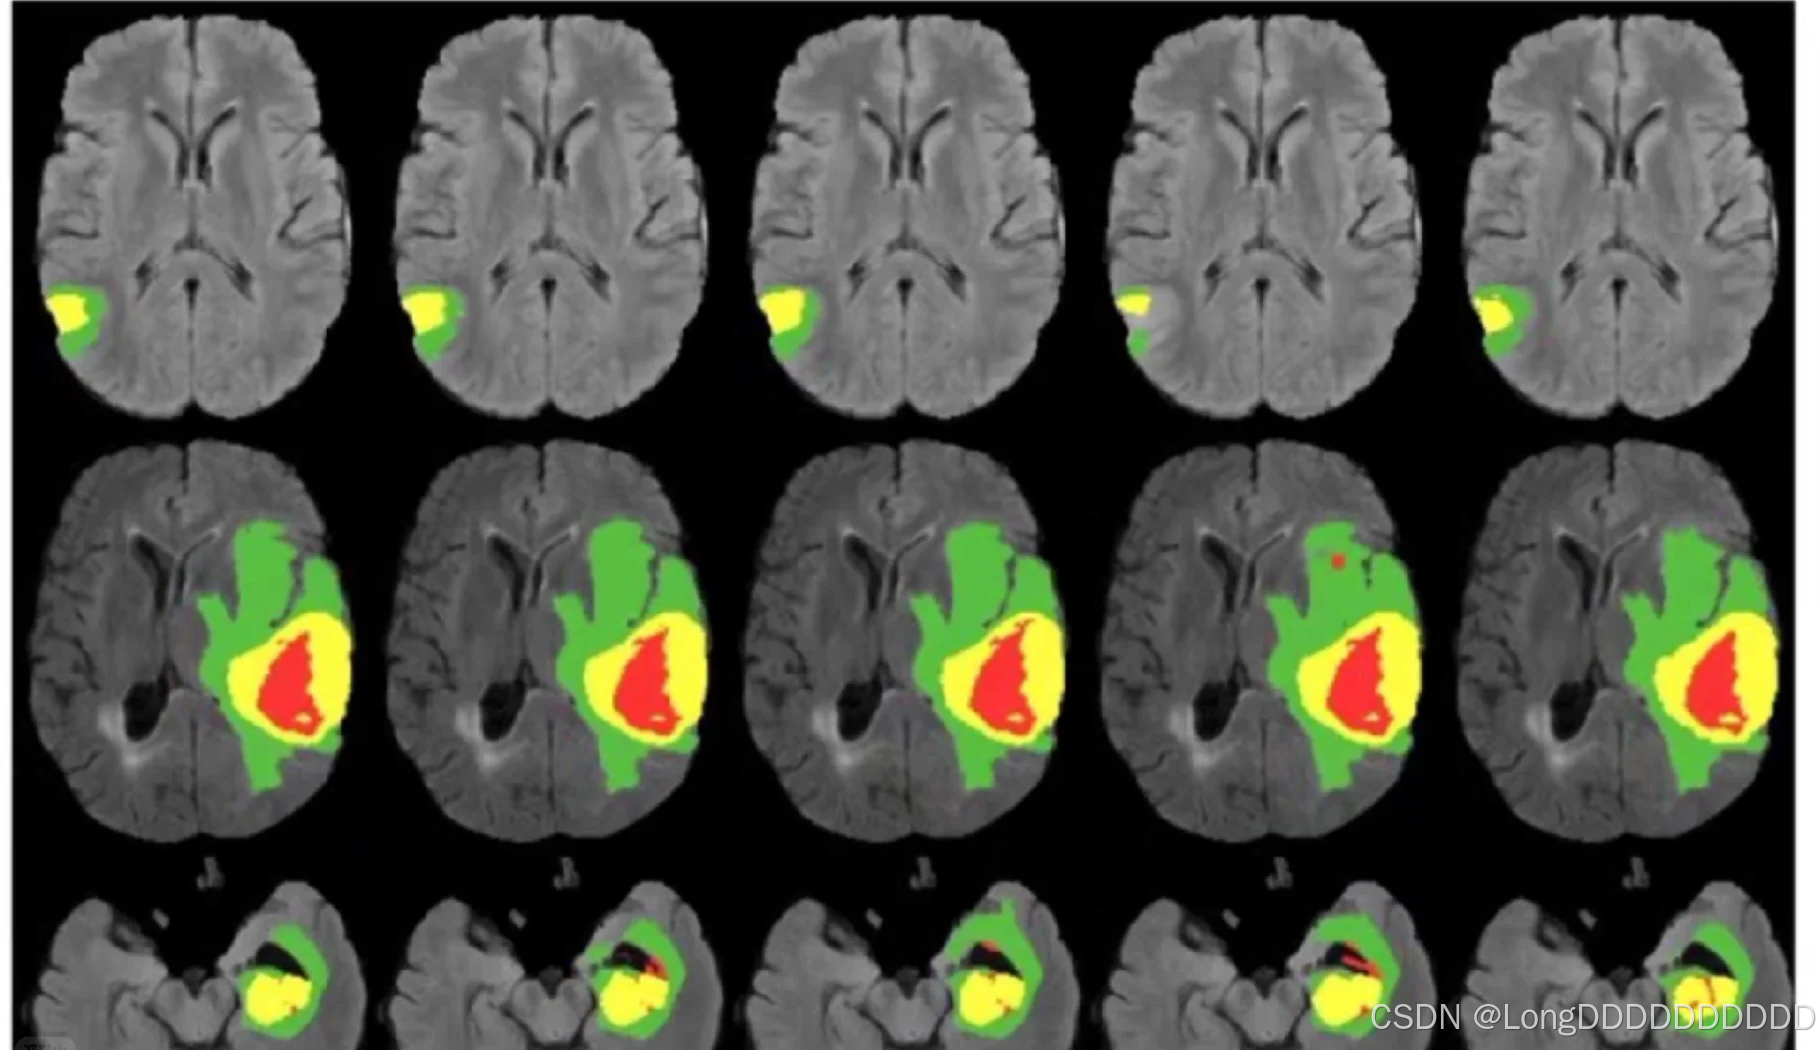

CT、MR、PET/CT等多模态图像能够同时展现病变的解剖结构和代谢信息。借助病变分割技术,我们能够更精确地呈现病变的形态及其与周围组织的毗邻关系,进而为临床诊断和治疗提供更为可靠的依据。然而,传统的图像分割方法主要依赖人工手动勾画,不仅操作繁琐,而且主观性强。随着人工智能技术的发展,特别是基于深度学习的卷积神经网络算法的应用,我们能够实现病灶的自动识别与勾画,从而显著降低主观因素的影响,提高图像分割的效率和可重复性。

磁共振(MR)图像具有序列多、信号复杂的特点。针对这些特点,人工智能能够迅速且精准地批量处理大量MR数据,在实现对不同病变的精确分割方面展现出巨大的应用潜力。Jünger等人针对非小细胞癌的315个脑转移瘤病灶,分别采用深度学习3D-CNN模型与手动分割方法进行对比研究。结果显示,3D-CNN模型的Dice相似系数(DSC)达到0.72,且其分割体积[(0.81±1.96) cm³]显著小于手动分割体积[(1.11±2.61) cm³],同时模型展现出高灵敏度(85.1%),表明该人工智能分割模型具备出色的分割效能。Yang等人则利用卷积神经网络在MR图像上分割肌肉组织,并计算肌肉在人体结构中的占比,以辅助诊断肌营养不良障碍。研究结果证明,该模型具有良好的准确度和灵敏度。由于MR对骨转移的诊断具有较高灵敏度,能够准确显示转移灶及周围软组织受侵犯情况。刘想等人通过训练3D U-Net模型,自动分割前列腺多参数MR中的弥散加权成像(DWI)和表观弥散系数(ADC)图像中的正常骨质结构,并认为双序列(DWI高+ADC)是3D U-Net分割盆腔骨质结构的最佳组合序列。

肿瘤病灶的分割以及边界定位对于术前评估切除范围以及放疗靶区的勾画具有至关重要的意义。PET/CT作为当前应用较为成熟的多模态影像技术,能够同时提供病变的解剖和代谢信息,这有助于临床医师更为精准地评估肿瘤的边界。相较于单纯的CT图像,PET/CT在确定肿瘤病灶轮廓以及定位正常组织与病变组织边界方面表现得更为准确。然而,手动分割方法耗时较长,因此临床上迫切需要一种人工智能自动分割方法。

有学者构建了基于脉冲耦合神经网络(Pulse Coupled Neural Network,PCNN)的模型,用于对PET/CT图像进行自动分割,并与常规的手动分割方法进行了对比。研究结果显示,PET自动分割的靶区与手动勾画的靶区高度一致,且其效果优于CT分割。特别是在区分肿瘤与肺不张时,PET自动分割肿瘤组织的精确度更高。在放疗靶区勾画方面,基于PET的放疗计划在正常肺组织的V20、V30指标上均显著低于基于CT的放疗计划。对于全身性疾病如淋巴瘤而言,图像的分割相较于单一病灶更为困难。